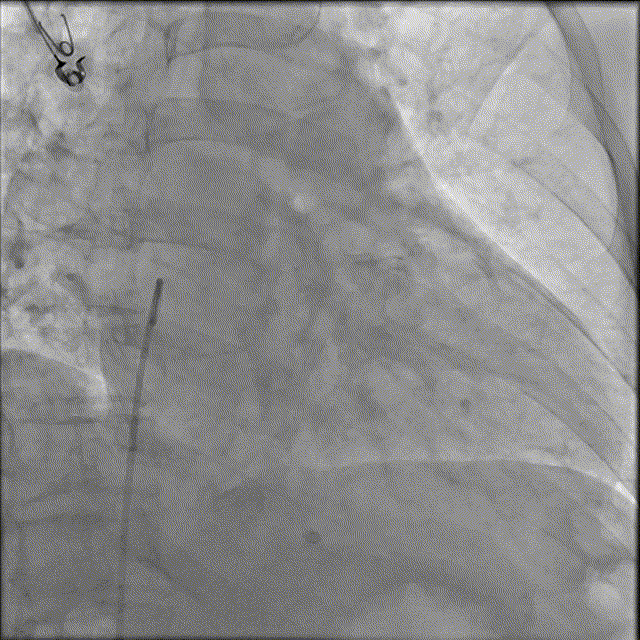

猪尾分别在RAO 30°、LAO 30°下造影,充分显示右心耳结构,为后续心房无导线进入提供参照。

心房无导线在下腔激活后,在RAO 30°下,略微施加调弯,操作导管将心房无导线送入右心耳基底部,RAO 30°、LAO 30°下造影确认心房无导线植入位置,位置非常好!